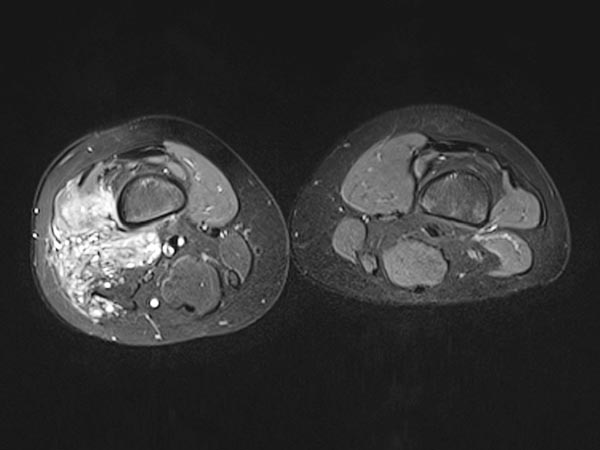

Die axiale T2-gewichtete MRT, fettunterdrückt, zeigt die nahe Lagebeziehung zum Periost des Femurs. Diese Lage ist besonders schmerzhaft durch entzündliche Reizung des Periosts.

Die T2-gewichtete MRT ohne Fettunterdrückung in axialer Schnittführung offenbart den entzündlichen, fibrotischen Umbau der Läsion durch multiple Entzündungen. Der rechte M. vastus lateralis des M. quadrizeps femoris ist komplett durchsetzt.